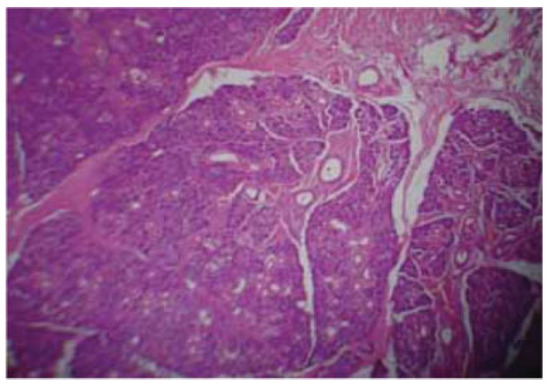

After superficial left parotidectomy, the mass was submitted for histologic analysis with final diagnosis of pleomorphic adenoma (Figure 3).

Figure 3. Histologic analysis after left superficial parotidectomy: epithelial elements are arranged in a variable background myxoid stroma and duct-like structures that consist of stellate-shaped cells of squamous metaplasia.